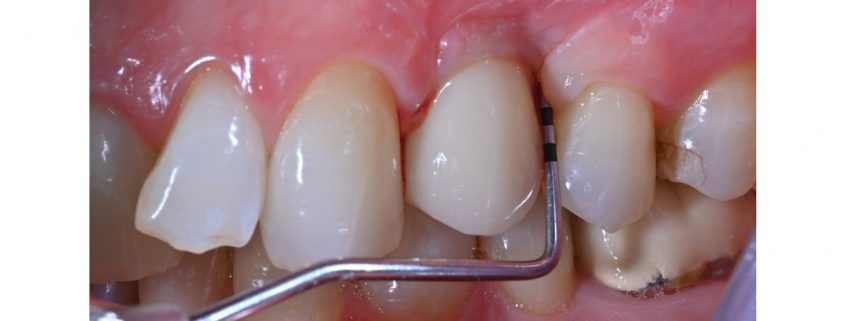

Vedlikeholds- og behandlingsstrategier for implantatpasienter med mucositt og peri-implantitt

Dette webinar tar for seg vedlikeholds- og behandlingsstrategier for implantatpasienter med mucositt og peri-implantitt, med tanke på å kunne oppnå et optimalt langtidsresultat. Målet er at du som kursdeltaker skal komme tilbake til klinikken og føle deg bedre rustet til å håndtere implantatkomplikasjoner og være tryggere på hvordan du kan unngå katastrofen. Du får med deg nye verktøy i din kliniske portefølje.